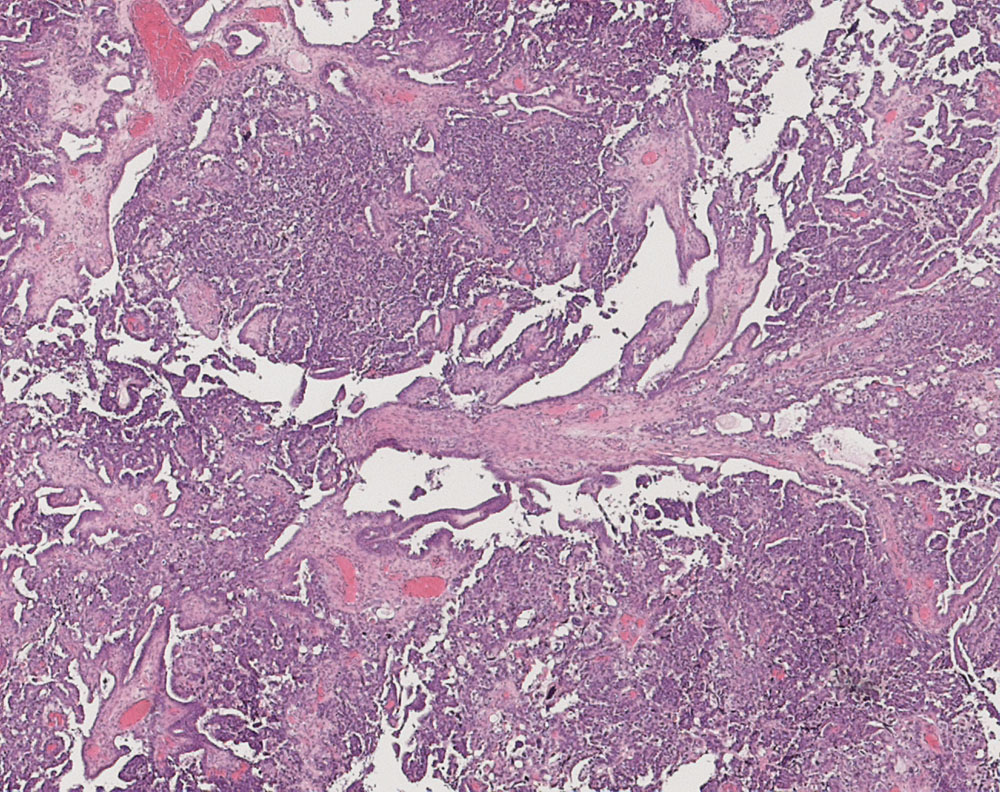

seröses Ovarialkarzinom high grade

Papillärer Tumor. Drüsen mit schlitzförmigen Lumina.

Verdacht auf Ovarialkarzinom (CA125 > 2000u/l). CT: Vergrösserte Ovarian beidseits. Maligner Pleuraerguss Adenokarzinom.

Histologie

25